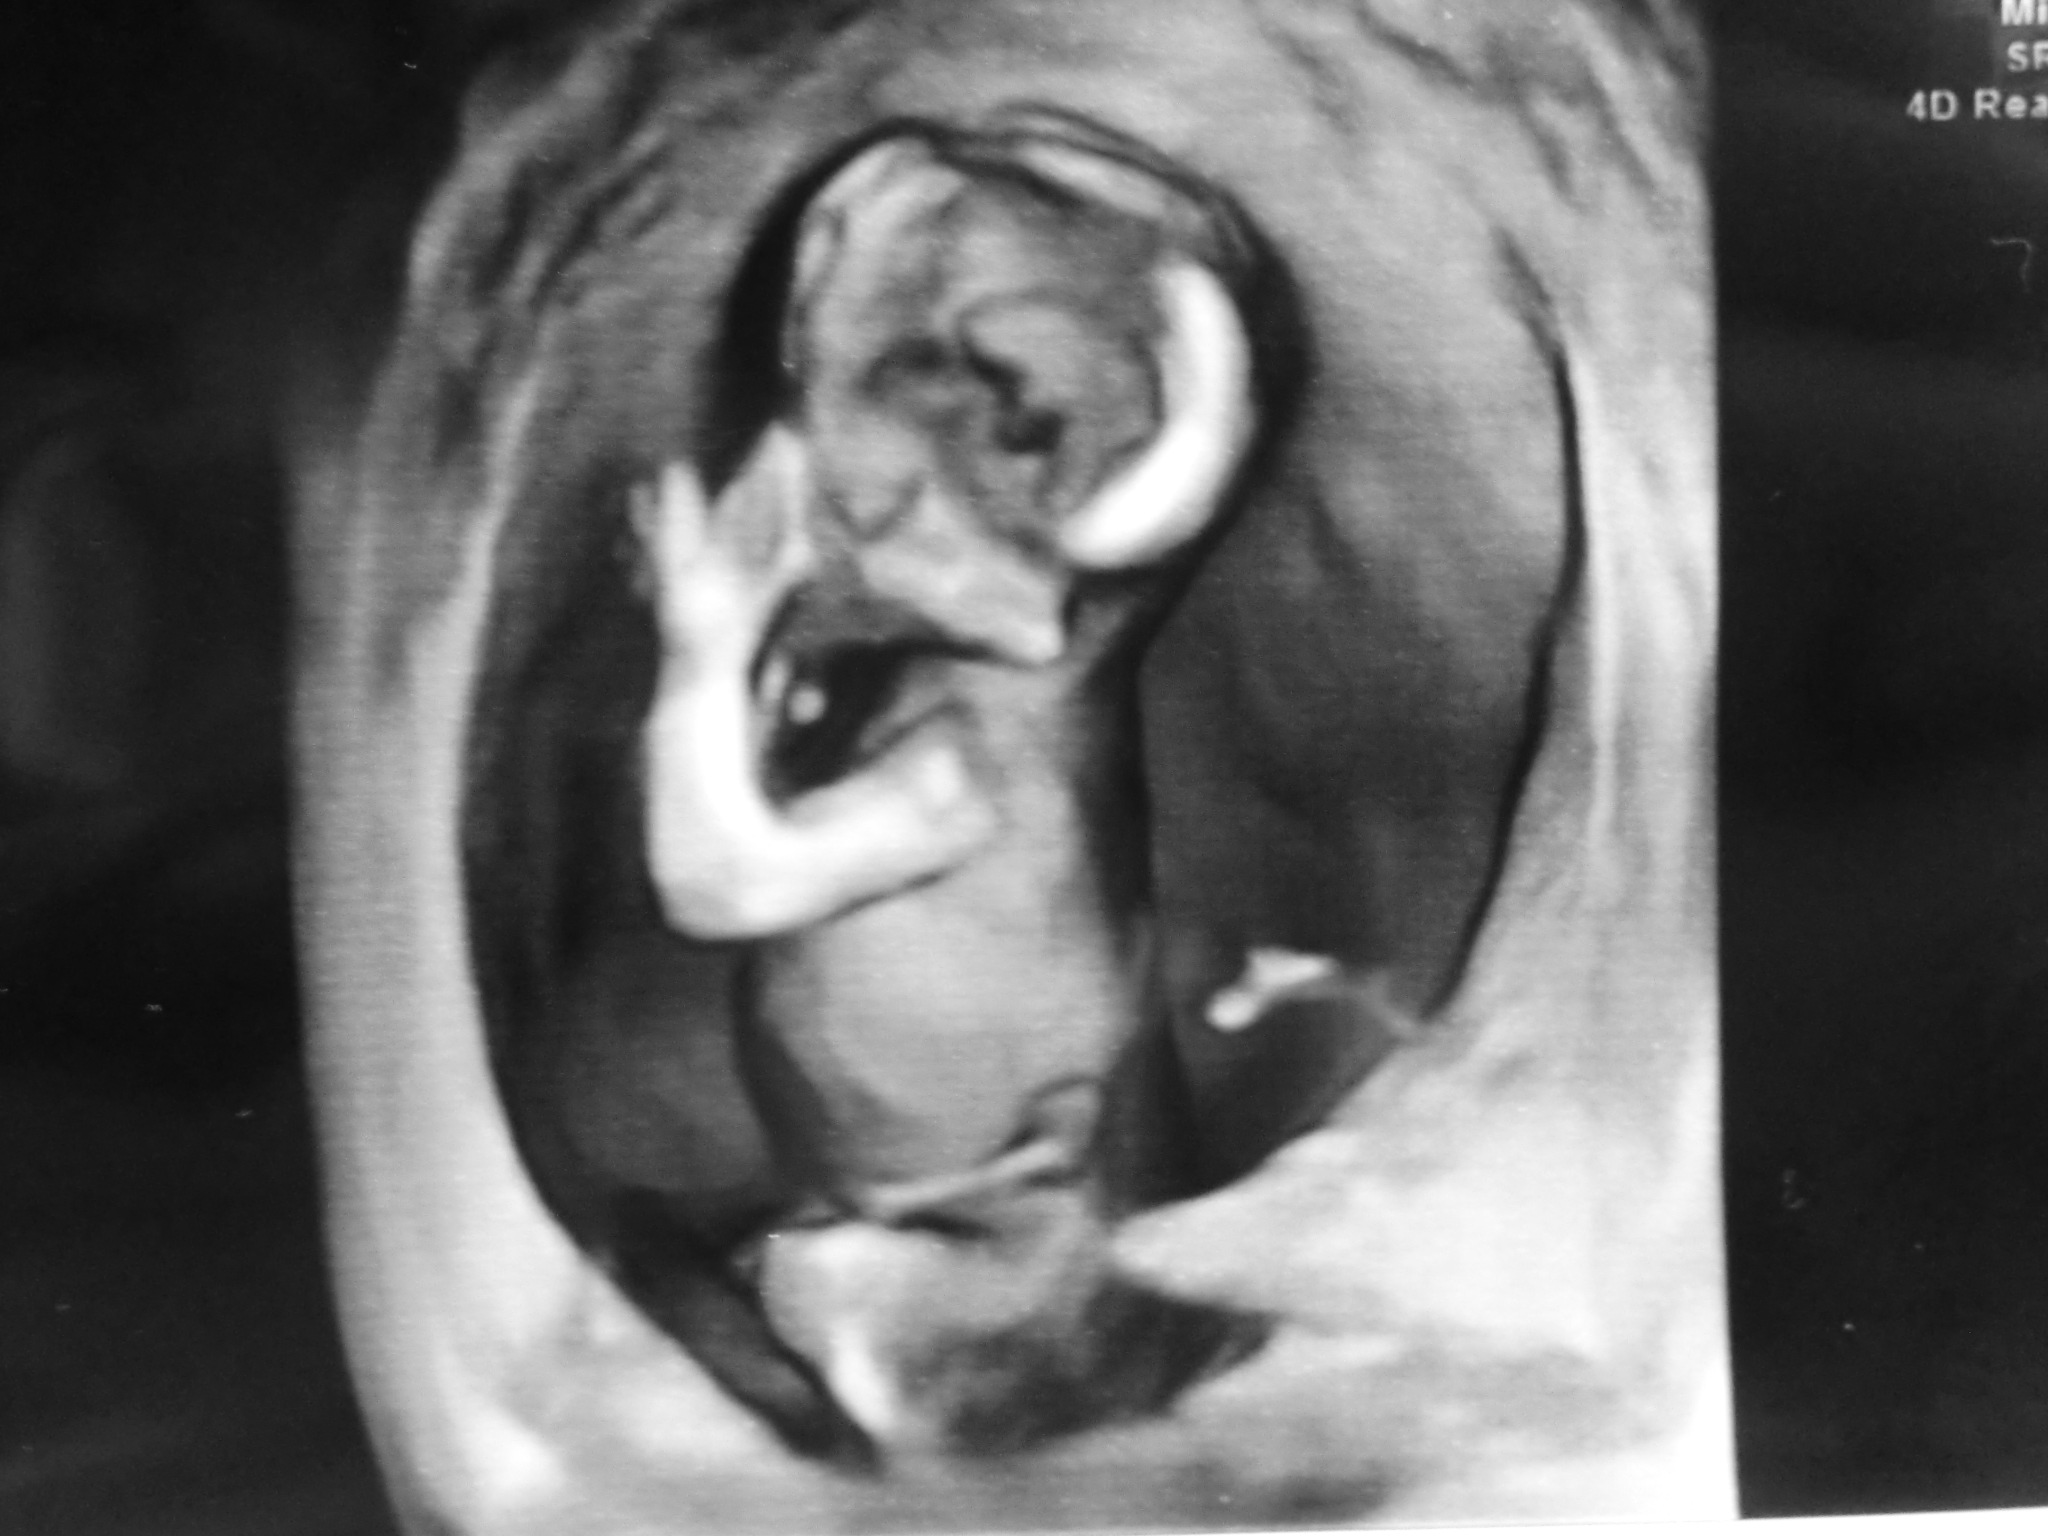

検診行ってきました。

今回からは股おっぴろげずに済みました。腹からエコー(でも思ってる以上にパンツめくらないといけないからあらわ)

今回から初の4D画像です!

モニターでは肌色というかオレンジ色というか、そういう色で動いてるのを見えてますが(動いてるのは前のでも見えてるけど)

印刷すると白黒です。(病院によるのかな?)

かわいいw

実母や実妹には親ばかだと散々バカにされました。

意味が分からない。かわいいじゃないか!プンスカ! 夫婦で怒っております。可愛いじゃないか!!

正座して、手を口元に当ててるんだぜ?

なんかお上品じゃないか!

先生がこの縦画像で見せてくれたけど、正しくは腹に対してうつぶせの体勢らしいですちょうど左が下になる。

体長10センチほどです。